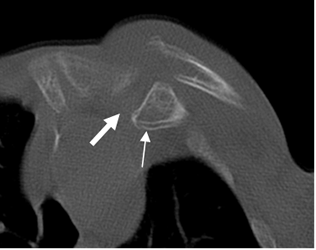

Fig 30 B. Luxofractura.

TAC axial. Fractura del tercio proximal de la clavícula, con desplazamiento inferior del fragmento (Flecha delgada) y subluxación de la articulación esternoclavicular. (Flecha gruesa).